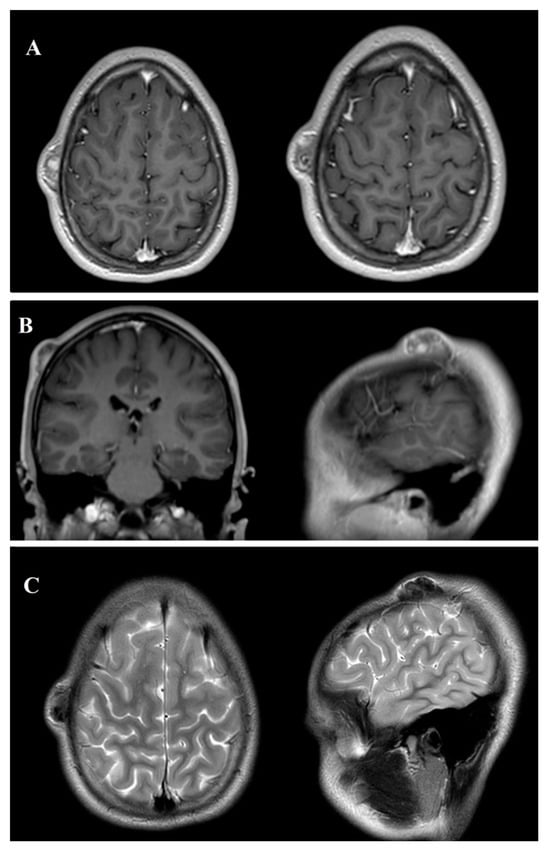

A preoperative MRI of the brain and cranial structures was performed using multiple sequences (SE, TSE, DWI, FLAIR, STIR, FFE, and 3D-TFE) before and after intravenous contrast administration. The imaging revealed a well-defined, expansile lesion measuring 30 mm anteroposteriorly and 9 mm craniocaudally, located in the subcutaneous soft tissues and closely adherent to the outer table of the right parietal bone. The lesion displayed marked contrast enhancement, suggestive of vascularity or active metabolic processes, with evidence of internal calcifications or hemosiderin deposits, indicating chronicity or previous microhemorrhages. Importantly, there was no invasion of the cranial bone or extension into adjacent soft tissues. The brain parenchyma, ventricular system, and major intracranial structures appeared normal, with no significant signal abnormalities or mass effects (Figure 2).

Figure 2. Preoperative magnetic resonance imaging (MRI) of an ossifying fibromyxoid tumor (OFMT) in the head and neck region, displayed in three key panels. Panel (A) shows axial T1-weighted sequences with gadolinium (Gd) contrast, highlighting the well-defined, expansile nature of the tumor with marked contrast enhancement, indicative of vascularity or metabolic activity. Panel (B) presents coronal and sagittal T1-weighted sequences with Gd contrast, offering a multi-planar view of the lesion’s relationship with the surrounding tissues and its anatomical boundaries. Panel (C) illustrates T2-weighted axial and sagittal sequences, where the tumor appears as a hyperintense mass, providing additional details on internal composition and fluid content. The combined imaging approach enables the precise characterization of the lesion’s location, structure, and extent, supporting preoperative planning and surgical decision-making.